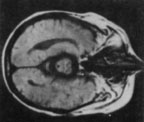

腦CT酒精中毒性神經疾病的中樞神經抑制症狀,應注意與引起昏迷的疾病相鑑別,如鎮靜催眠藥中毒、一氧化碳中毒腦卒中、顱腦外傷等戒斷綜合徵的精神症狀和癲癇發作,應與精神病、癲癇、窒息性氣體中毒低血糖征等相鑑別慢性酒精中毒的智慧型障礙和人格改變,應與其他原因引起的痴呆鑑別。

其它輔助檢查:1.心電圖、腦電圖、腦CT或MRI檢查,有鑑別診斷及中毒程度評估意義;2.肌電圖和神經電生理檢查有鑑別診斷意義。